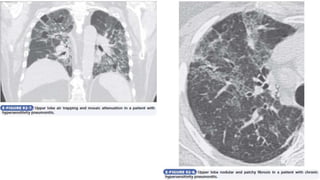

• On HRCT, small centrilobular ill-defined nodules of ground-glass

densities are seen, along with evidence of mosaic attenuation

(trapped air) as a result of concomitant bronchiolitis and upper lobe

predominance of the parenchymal abnormalities. Chronically, findings

of lung fibrosis may be indistinguishable from the patterns seen in

usual interstitial pneumonia and idiopathic pulmonary fibrosis